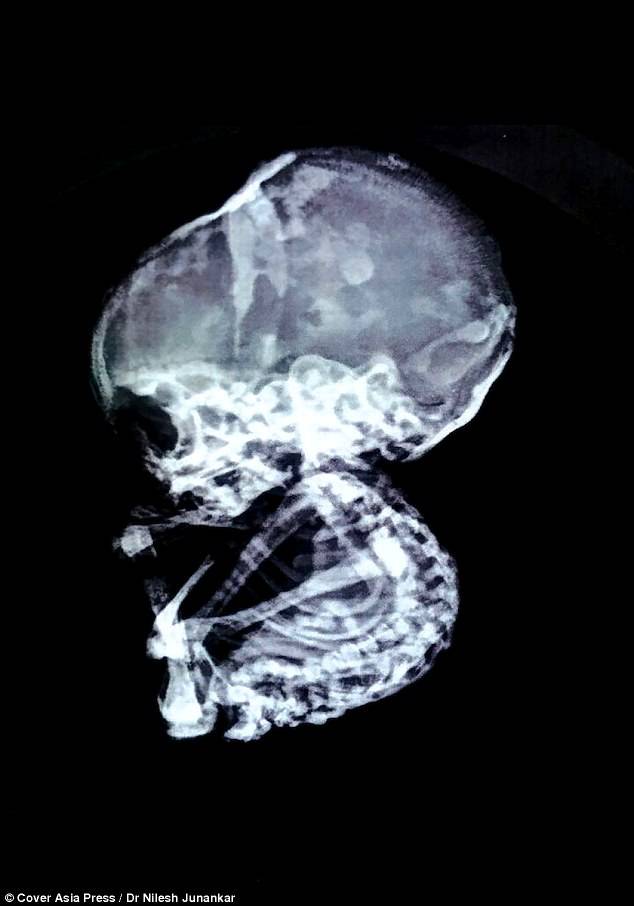

Dopo essersi rivolta all’ennesimo specialista la signora indiana ha scoperto di aver portato dentro di sé un feto calcificato da 15 anni.

Il dottor Nilesh Junanka, chirurgo laparoscopico, ha commentato: “le scan hanno mostrato un’ostruzione intestinale, un blocco nell’esofago che somigliava a una struttura di pietra”.

Quando è stata effettuata una laparoscopia si è scoperto che c’era un bambino calcificato di 4 mesi nell’addome.

La donna è stata subito operata. “Dopo aver aperto l’addome abbiamo trovato un intero bambino di pietra. Comunque il suo utero, le ovaie e le Tube di Falloppio erano completamente normali”.

Un bambino di pietra o litopedio è una condizione estremamente rara. Negli ultimi 400 anni sono stati registrati solo 300 casi.